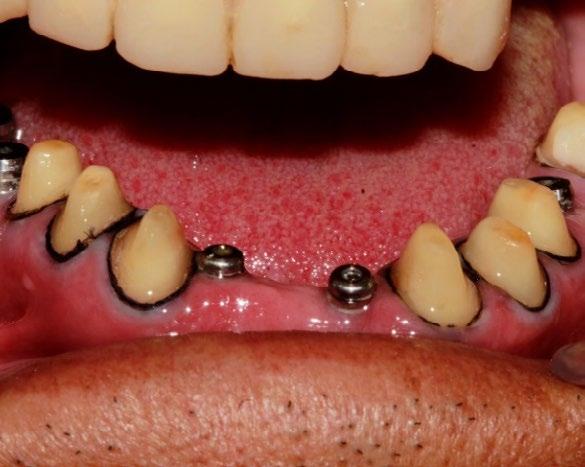

Figura 5. Primera fase quirúrgica de implantes dentales y segunda fase quirúrgica de colocación de tornillos de cicatrización en la zona de los O.D. 16, 15, 24, 26, 36, 32, 42, 46 y 47.

Se montaron los modelos de estudio en un articulador semiajustable Axiomath, aumentando 0.4 mm de DV. Con base en esto, se realizó el encerado diagnóstico (Figura 3). En la fase preventiva, se llevó a cabo una profilaxis con ultrasonido. Posteriormente, se realizaron extracciones de piezas dentarias con mal pronóstico. Se elaboró una guía de silicona basada en el encerado diagnóstico para el mock-up,

En la primera fase quirúrgica se colocaron los implantes dentales en las zonas de las piezas 16, 15, 24, 26, 36, 32, 42, 46 y 47. A los 6 meses se evaluó la osteointegración hueso-implante, y

Figura 6. Desgaste de los O.D. 17, 13, 12, 11, 21, 22, 23, 37, 35, 34, 33, 43, 44 y 45 para prótesis fijas estéticas.

posteriormente se procedió a la segunda fase quirúrgica con la colocación de tornillos de cicatrización (Figura 5). En la fase protésica, se procedió al desgaste de las piezas para las prótesis fijas (Figura 6), se tomaron impresiones a 2 pasos con doble hilo retractor, y se enviaron al laboratorio dental para la elaboración de coronas de E-max. Mientras tanto, se colocaron restauraciones provisionales. Posteriormente, tras el cementado de las restauraciones definitivas (Figura 7), se procedió a la rehabilitación sobre implantes. Se tomaron impresiones a cucharilla abierta, que se enviaron al laboratorio para la elaboración de coronas sobre implante. Se realizó la prueba de biscocho, analizando la oclusión, y luego se reenviaron al laboratorio.

Finalmente, al recibir las coronas sobre implantes, se fijaron las restauraciones con un torque de 25 newtons, dejando las piezas sobre implantes en desoclusión (Figura 8).